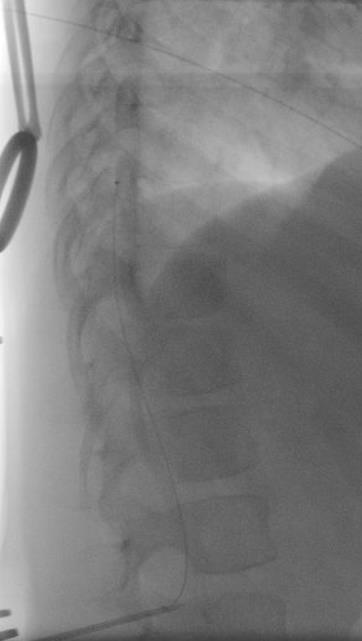

Adductor Longus L2, L3

Vastus Lateralis L3,L4

Tibialis Anterior L4, L5

Peroneus longus L5, S1

Gastrocnemius S1, S2

Abductor hallucis S1, S2

Sphincter S2